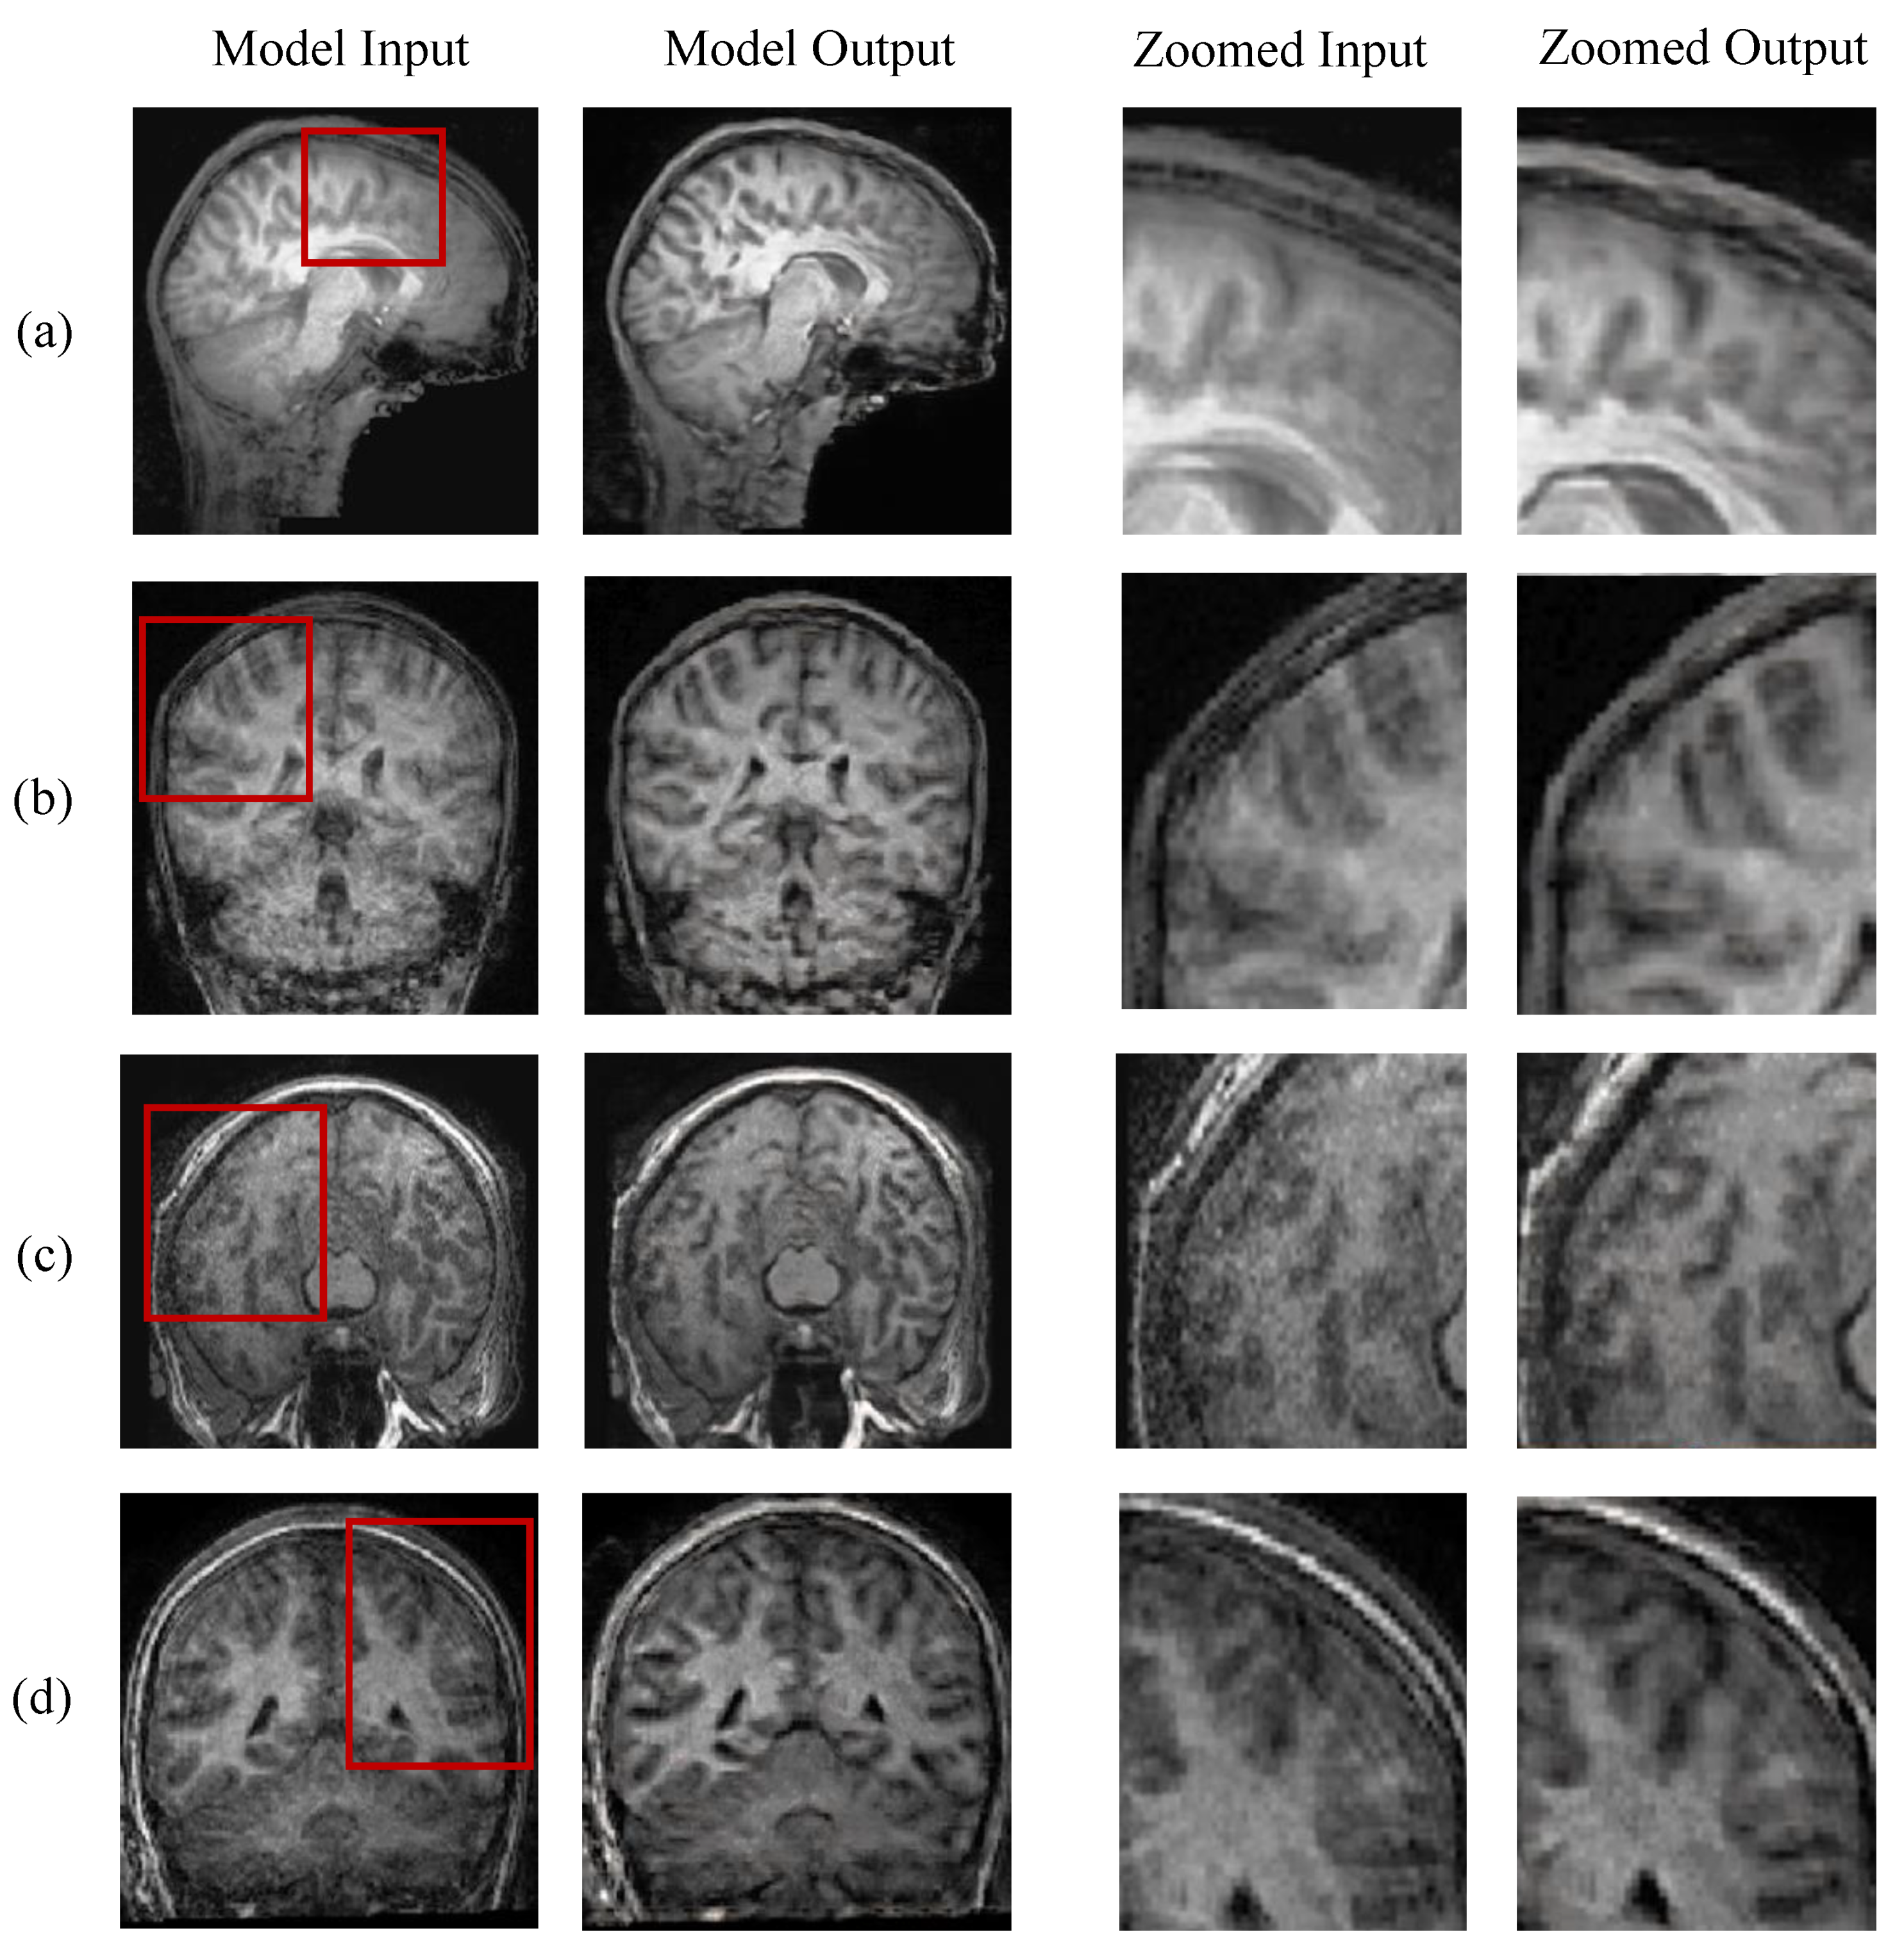

5.3. Evaluation on Real-World Scans